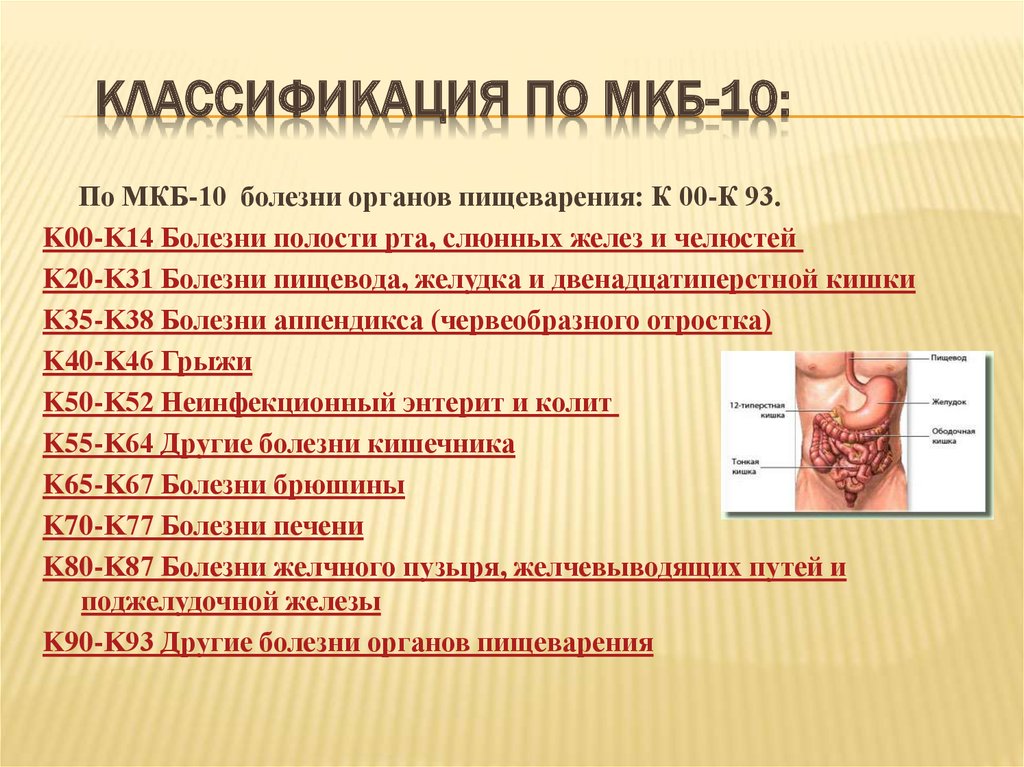

Код мкб 10 атерома головы

Код мкб 10 атерома головы 109 фото